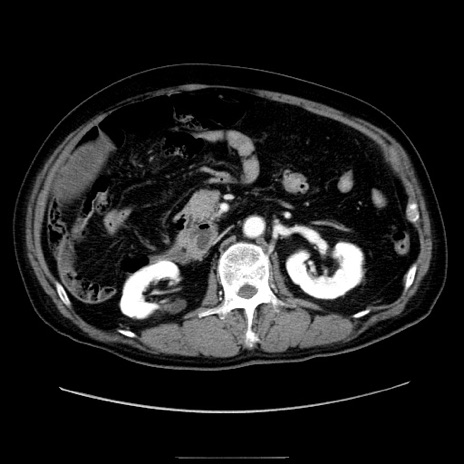

症例30(横断像)

【症例】80歳代男性

【主訴】臍周囲痛

【現病歴】約6時間前から臍下部痛が出現。次第に腹部膨隆・背部痛も生じてきたため来院。背部痛の場所は変化しない。

【既往歴】腎盂腎炎

【身体所見】意識清明、BT 36.3℃、BP  131/87mmHg、P 87bpm、SpO2 100%(RA)、臍周囲自発痛・圧痛あり、反跳痛なし、自発痛部位に一致して板状硬あり、腹部膨隆、腸雑音減弱、CVA tenderness両側陰性。

【データ】WBC 19600、CRP 0.33